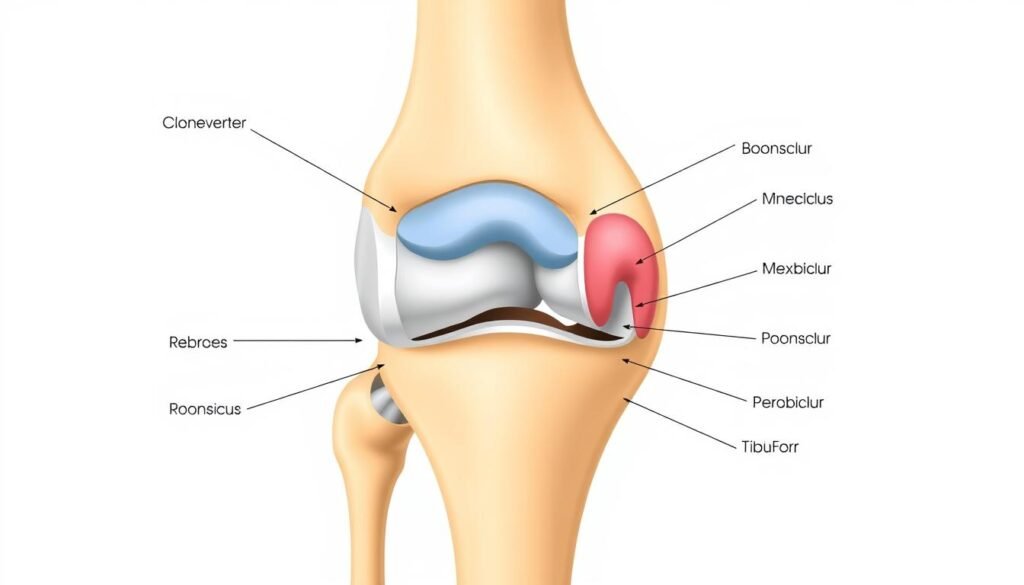

Klinische Untersuchung: Der Apprehension-Test zur Überprüfung der Kniescheibenstabilität